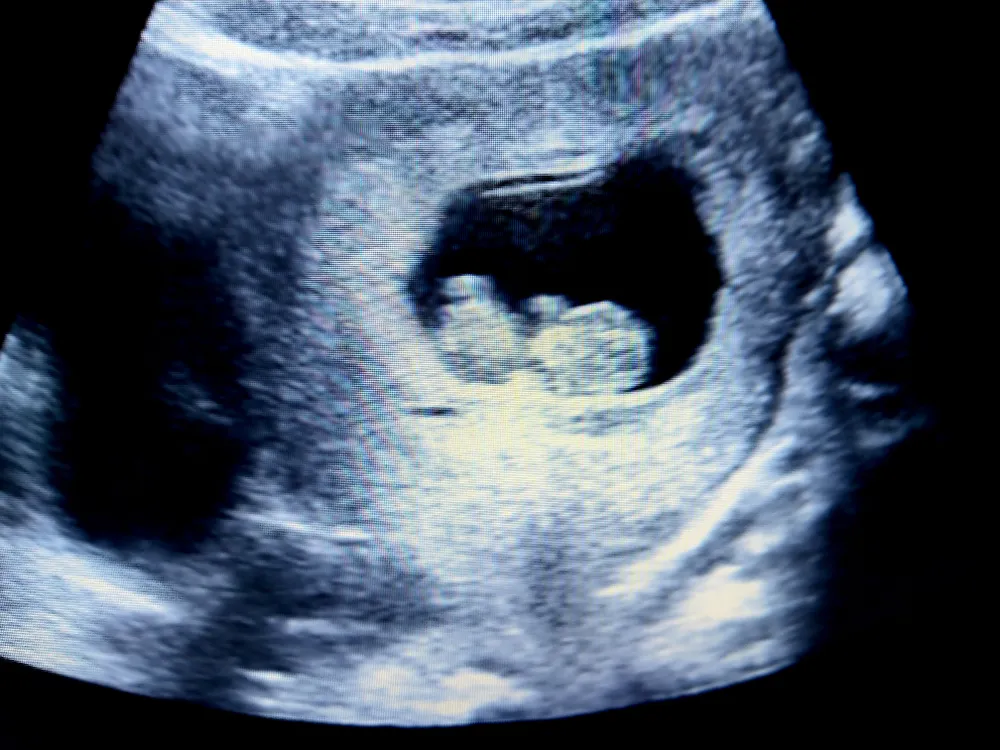

1. Hình ảnh siêu âm thai 10 tuần tuổi như thế nào?

Thai nhi tuần 10 có kích thước cỡ quả anh đào, chiều dài khoảng 3 – 3.5cm và nặng khoảng 0,008kg (8g). Tư thế của thai nhi có tay chân hơi co vào thân mình, lưng có thể cong hoặc thẳng, đầu khi cúi khi ngửa. Các cử động của thai nhi tương đối nhiều, chân tay cũng phát triển rõ hơn và có cử động gập duỗi.